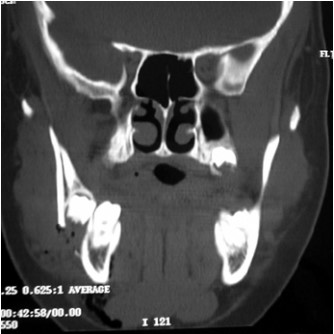

Fig 1: 3D C.T of displaced mandibular angle fracture

In this study, 7 cases associated with impacted third molar represented sever displacement of the angle fracture (figure 1, 2) and interfered with achievement of reduction. In four cases, extraction of the impacted lower third molar was done to achieve good reduction at the fracture site. The remaining three cases that were treated without extraction of the lower third molar required more time to obtained good reduction (time range from 30-45 minutes) and exhibited postoperative infection and delayed healing in the fracture site and underwent a second operation for removal of the lower third molar.

Only two cases without lower third molar in the fracture site represented sever displacement of the angle fracture (figure 4).